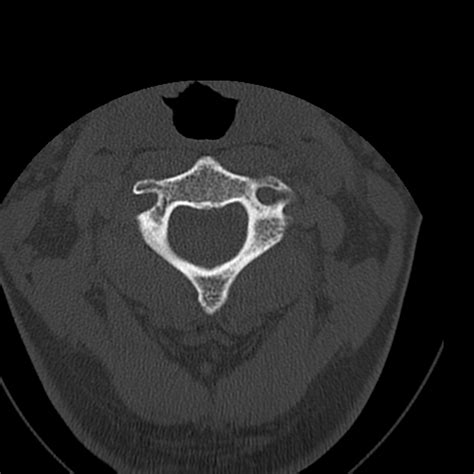

• Computed Tomography (CT) Scan: This is the gold standard for diagnosing occipital condyle fractures. CT scans provide detailed images of the bony structures and can help identify the location and extent of the fracture.

• occipital condyle on ct scan